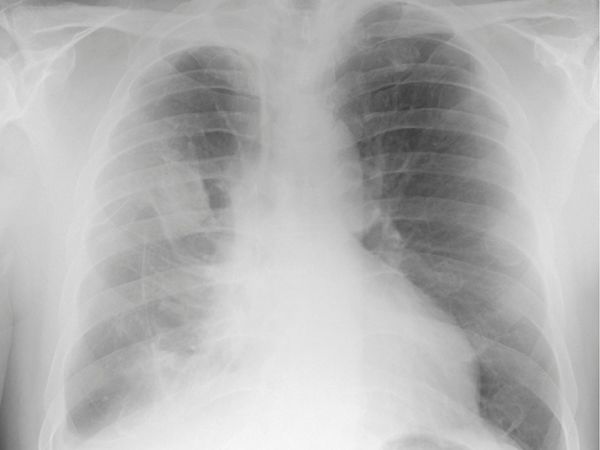

Radiographie pulmonaire montrant des plaques pleurales

Le cancer broncho-pulmonaire

Le cancer broncho-pulmonaire est le cancer le plus fréquent dans la population masculine mondiale, il représente 10 % des décès masculins dans les pays industrialisés. Il est lié à différents facteurs, principalement le tabac qui serait responsable de 80 % des cas. L’inhalation de fibres d’amiante est également responsable de cancers broncho-pulmonaires, avec un ratio cancers pulmonaires / mésothéliomes de l’ordre de 3,5. L’exposition aux fibres d‘amiante multiplie le risque de cancer pulmonaire par 5, alors que ce facteur est de 10 pour l’exposition au tabac. Les effets du tabac et de l’amiante sont indépendants l’un de l’autre c’est à dire que donc le risque est multiplié par 50 en cas de double exposition: tabac + amiante.

Cancer Broncho-pulmonaire (vue illustrative)